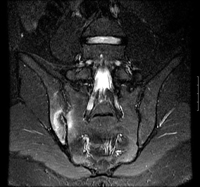

Sacroileíte

História

dorsalgia, talvez dor nos membros inferiores

Exame físico

sensibilidade à palpação na articulação sacroilíaca; o teste de impulsão da coxa, o teste de distração, o teste de Gaenslen, o teste de compressão pélvica e/ou o teste FABER podem ser positivos. Três ou mais testes positivos indicam que a ASI é provavelmente a causadora da dor

Primeira investigação

- nenhuma:

Outras investigações

- radiografias simples:

em geral, nenhuma outra anormalidade é observada

- injeção de bloqueio anestésico local diagnóstico para articulação sacroilíaca com orientação fluoroscópica do braço C:

diminuição significativa da dor após injeção da articulação sacroilíaca